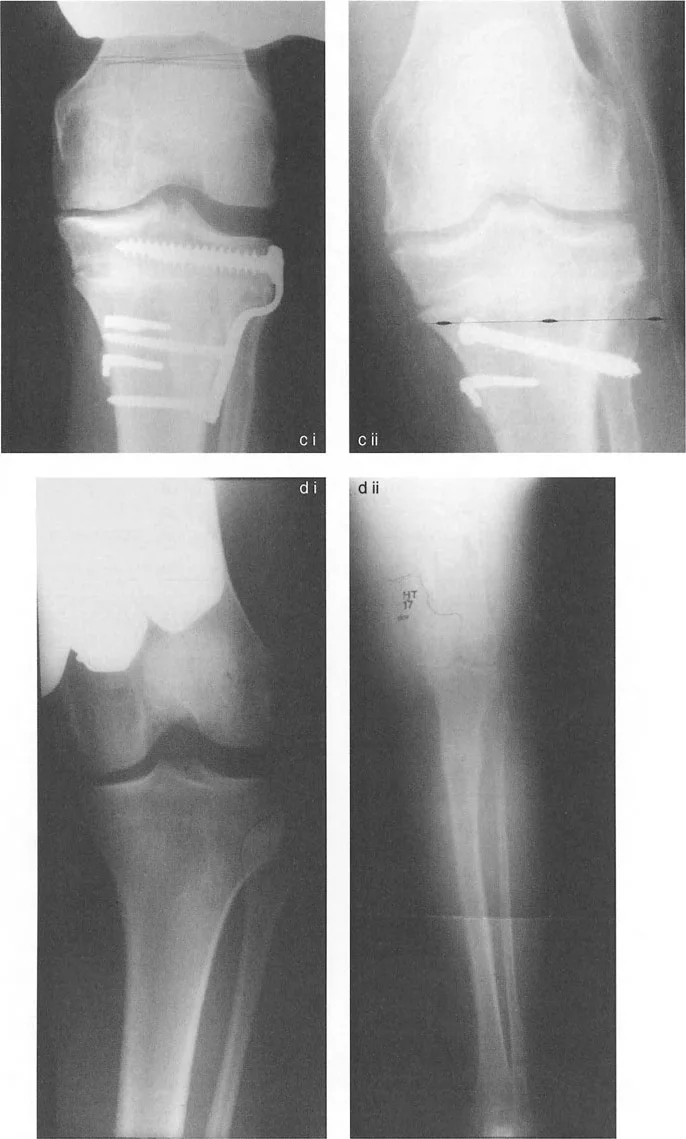

التصوير الإشعاعي المتقدم: مفتاح فهم التشوه

لا يمكن الحكم على المحاذاة والاتجاه بدقة إلا باستخدام صور الأشعة السينية الطويلة للطرف السفلي بالكامل في وضع الوقوف (فيلم بطول 51 بوصة). الأفلام التي تُؤخذ والمريض مستلقٍ أو أفلام الركبة القصيرة غير كافية تمامًا لتخطيط تصحيح التشوه.

نصائح مهمة للأشعة السينية الدقيقة:

- توجيه الرضفة: الدوران الصحيح للطرف أثناء الأشعة السينية أمر بالغ الأهمية. تكون الأشعة السينية صالحة فقط إذا كانت الرضفة متمركزة تمامًا بين لقمات الفخذ وموجهة للأمام مباشرة.

- وضع القدم غير ذي صلة: لا تضع المريض بناءً على زاوية تقدم القدم. إذا كان المريض يعاني من التواء في الساق للخارج، فإن وضع القدم للأمام سيؤدي إلى دوران داخلي للركبة، مما يبطل تمامًا قياسات مستوى التاج. دائمًا ما تُؤخذ الأشعة السينية بناءً على الركبة (الرضفة للأمام).

- ارتفاع الشعاع: يجب أن يتمركز شعاع الأشعة السينية عند مستوى مفصل الركبة من مسافة قياسية (عادة 10 أقدام) لتقليل أخطاء التكبير والتزيح.